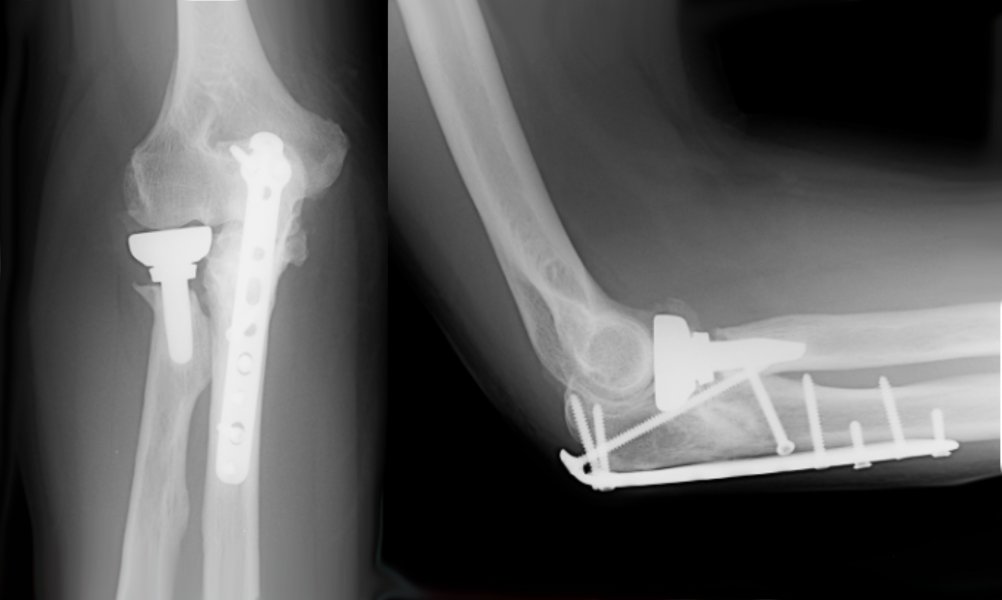

The operation is performed under a combination of general and regional anaesthesia. The fracture of the ulna is exposed, the bone fragments realigned and then fixed with a plate and screws. The fracture of the radial head may be fixed with a plate or screws if the pattern is simple. In instances where the fracture of the radial head is not reparable, a radial head replacement may be performed.